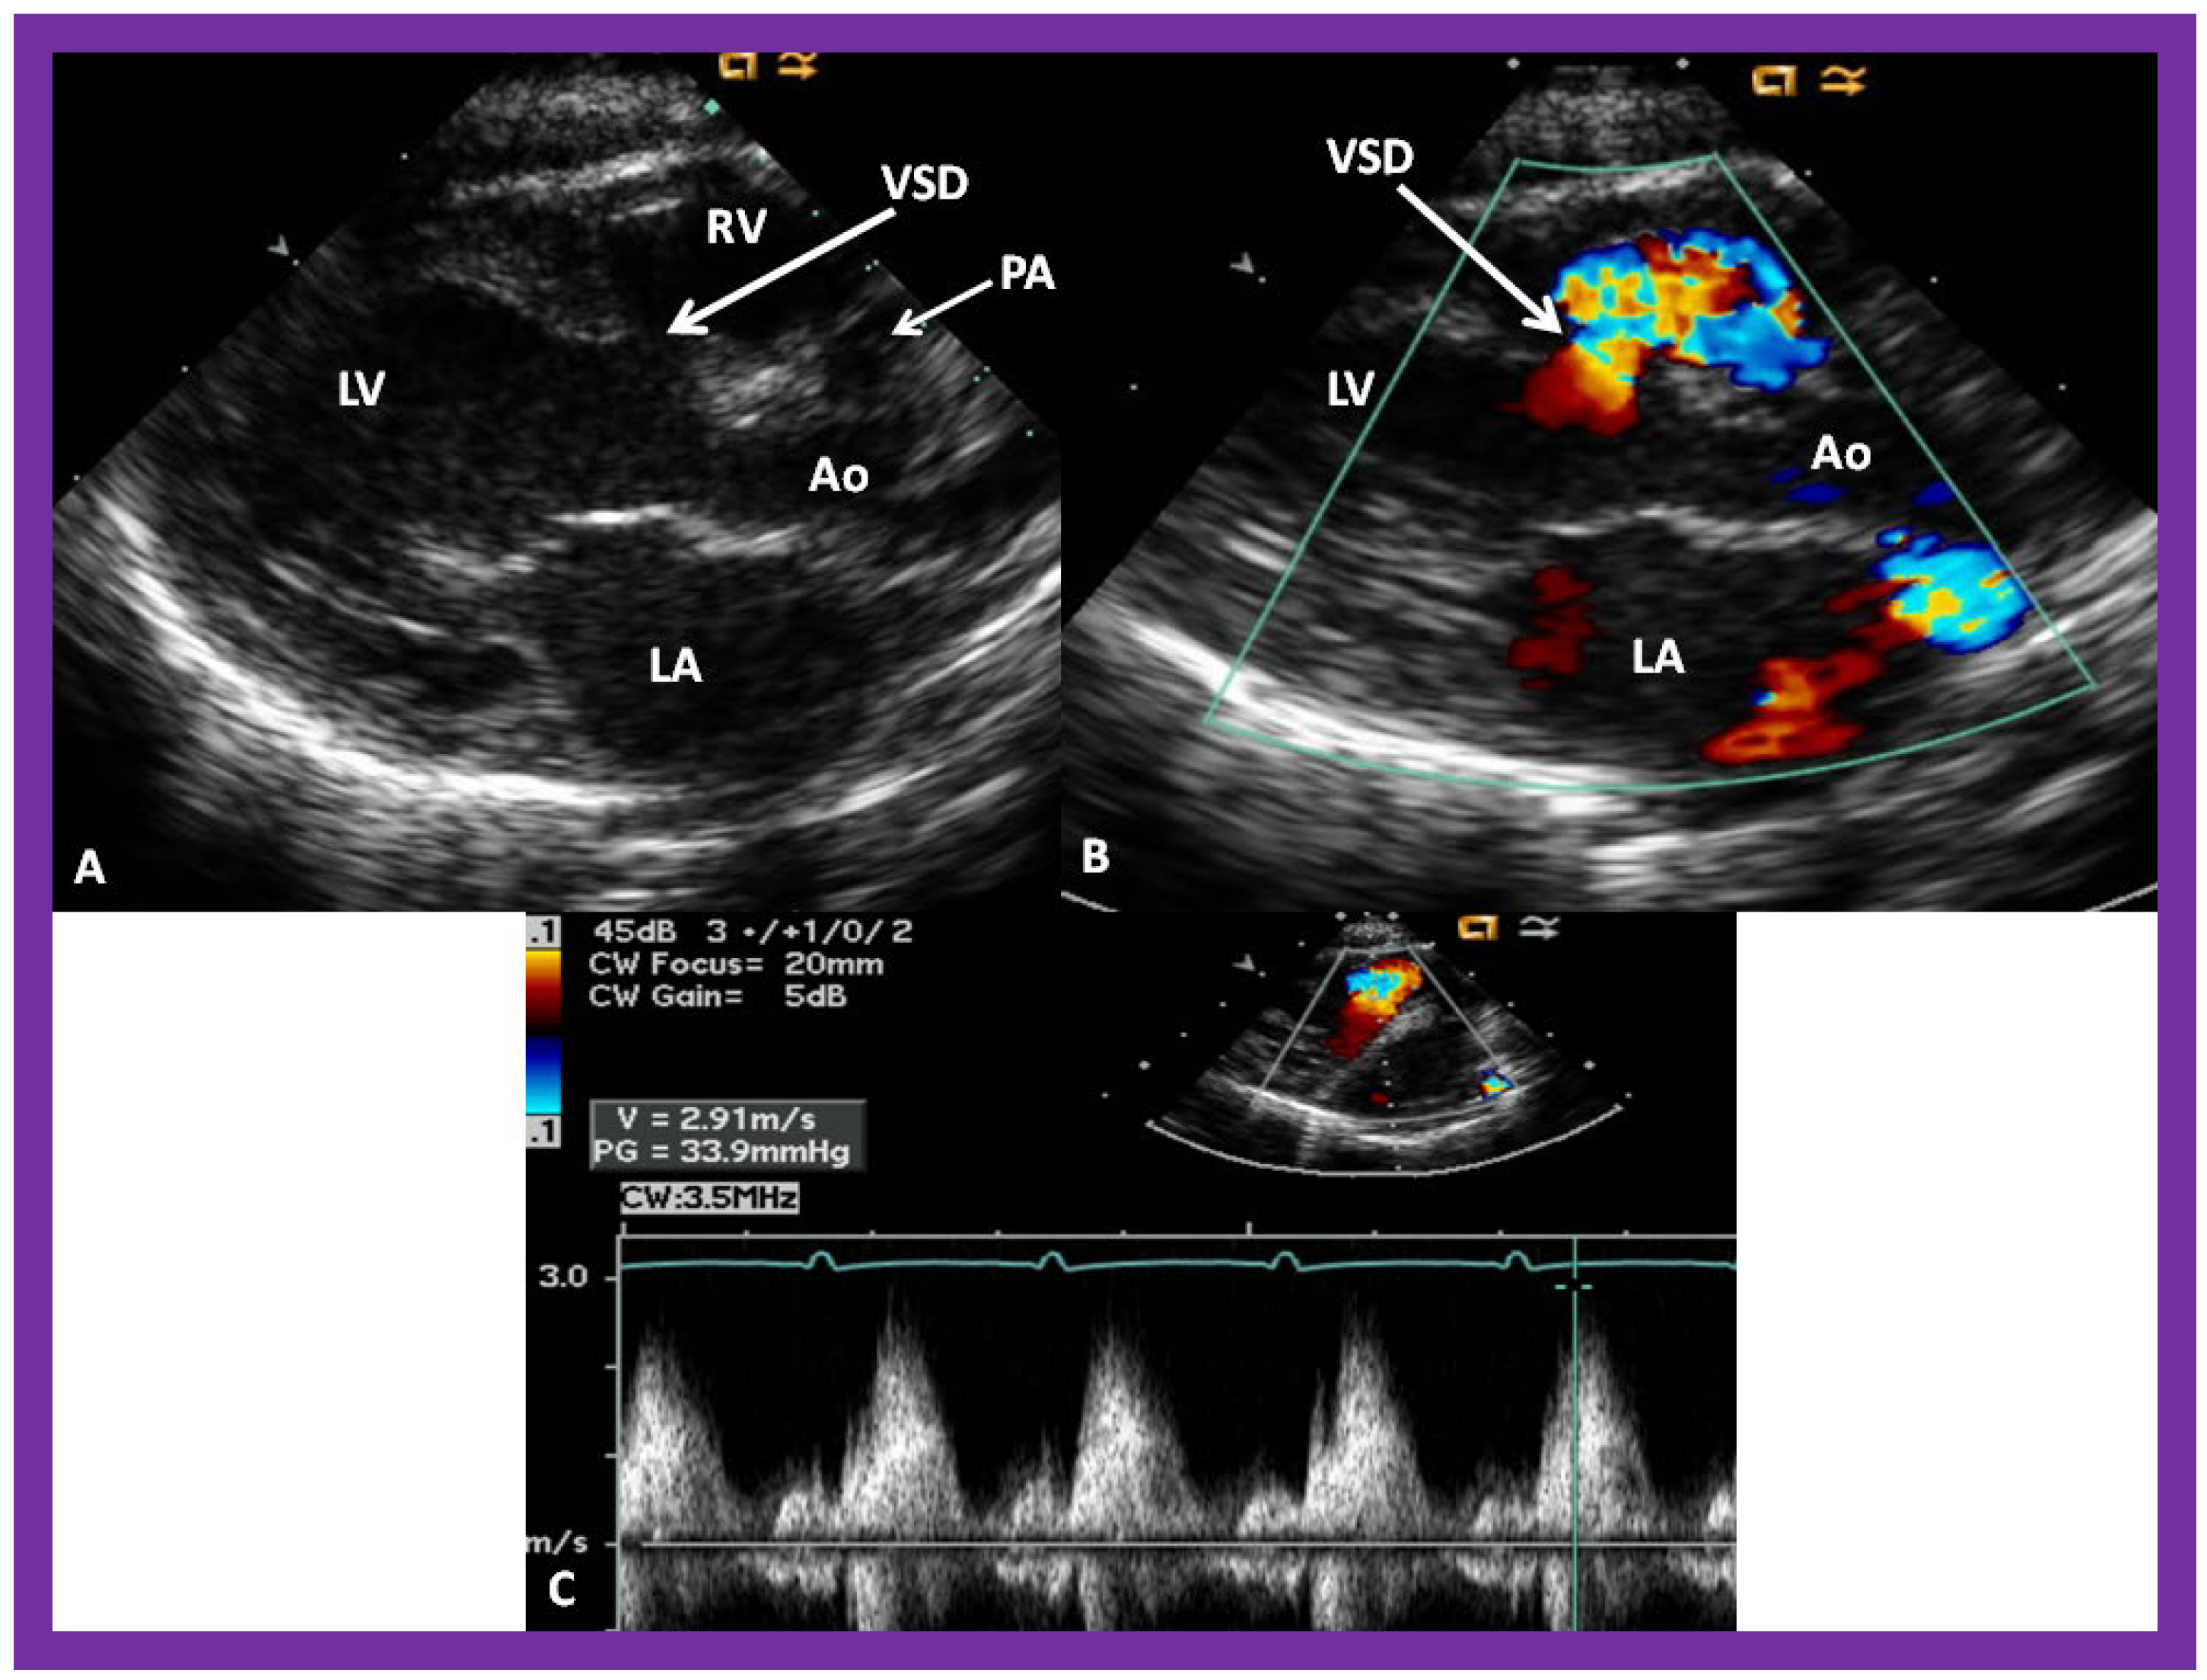

Figure 6. (A) A selected video frame from parasternal long axis views of a patient with tricuspid atresia and transposition of the great arteries demonstrating the left atrium (LA), left ventricle (LV), a very small right ventricle (RV) and a moderate sized ventricular septal defect (not marked). The vessel coming off the LV is traced in (B) and shown to bifurcate into the left (LPA) and right (RPA) pulmonary arteries, confirming that this vessel is the main pulmonary artery (MPA), consistent with transposition of the great arteries. Ao, Aorta. Reproduced from Reference [21].

Figure 7. A selected video frame from a parasternal long axis view with color flow mapping of another patient with tricuspid atresia and transposition of the great arteries demonstrating the left atrium (LA), left ventricle (LV), a small right ventricle (RV) and a moderate sized ventricular septal defect (VSD). The vessel coming off the LV bifurcates into right (RPA) and left (LPA) pulmonary arteries. Reproduced from Reference [21]. PA, pulmonary artery.